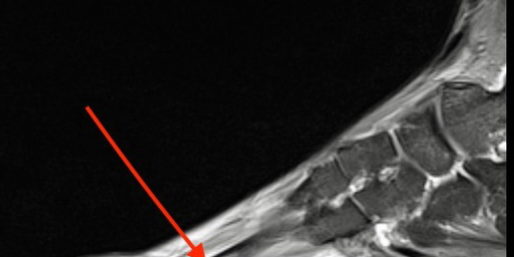

Najprostszym i zarazem najbardziej dostępnym badaniem jest zdjęcie radiologiczne. Tu jednak zmiany obrazie rtg widoczne są na późnym etapie choroby, kiedy to formuje się już wyraźna blizna kostna. Obecnie, w diagnostyce uszkodzeń zmęczeniowych kości, metodą o wysokiej czułości i swoistości, jest badanie rezonansu magnetycznego. Badanie to pozwala uwidocznić uszkodzenie już na wczesnym etapie choroby, kiedy nie dochodzi jeszcze do złamania. Coraz większa dostępność rezonansu magnetycznego czyni go wręcz badaniem podstawowym w diagnostyce uszkodzeń zmęczeniowych kości. W oparciu o skany badania rezonansu w 2013 Nevitt i wsp. opracował stopniową skalę uszkodzeń kości (patrz tabela 1) (8).

4 stopnie klasyfikacji uszkodzeń pozwalają różnicować uszkodzenia już na wczesnym etapie, co jest bardzo pomocne dla lekarza, ponieważ w stopniach 1-3 skali nie widzimy jeszcze lini złamania.

Klasyfikacja uszkodzeń kości w obrazie rezonansu wg Nattiv i wsp 2013

| Stopień 1 | niewielki obrzęk szpiku lub okostnej w sekwencji T2, sekwencja T1 prawidłowa |

| Stopień 2 | umiarkowany obrzęk szpiku lub okostnej w sekwencji T2, sekwencja T1 prawidłowa |

| Stopień 3 | nasilony obrzęk szpiku lub okostnej w obu sekwencjach T1 i T2 |

| Stopień 4 | nasilony obrzęk szpiku lub okostnej w obu sekwencjach T1 i T2, widoczna linia złamania |

Tabela 1. Skala uszkodzenia kości w badaniu rezonansu magnetycznego wg Nattiv.